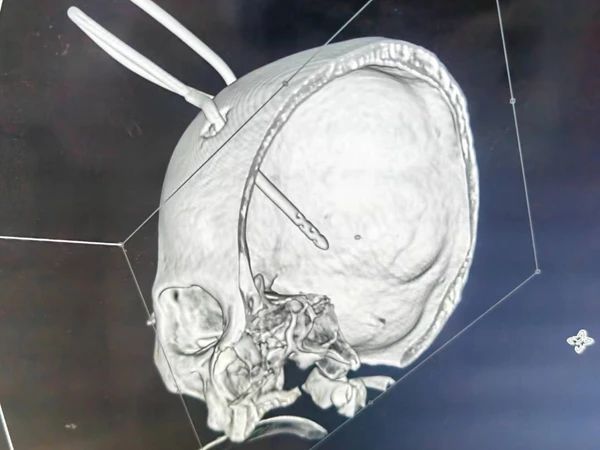

在刘展会主任“一站式”破裂动脉瘤治疗理念的指导下,术后立即为患者行脑室外引流,尽快将脑室积血、蛛网膜下腔出血引流出来。术后病人很快恢复了意识,一周后脑室积血及蛛网膜下腔出血基本清除,继续康复治疗。